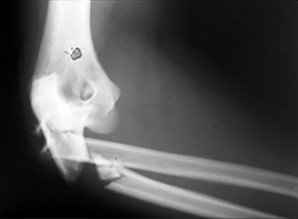

- الأشعة السينية (X-rays): هي الخطوة الأولى في تقييم الكسور، الخلوع، وتغيرات التهاب المفاصل. تساعد في تحديد مدى تدهور العظام والمسافات المفصلية. على سبيل المثال، تُظهر صور الأشعة السينية كسور السلاميات

أو كسور قاعدة العظم المشطي الخامس

، بالإضافة إلى علامات مثل "الدمعة الشعاعية" (Radiographic Teardrop) في الرسغ التي تمثل الزاوية الزندية الراحية الحرجة للكعبرة البعيدة

. - الأشعة المقطعية (CT Scan): توفر صوراً تفصيلية ثلاثية الأبعاد للعظام، وهي مفيدة جداً لتقييم الكسور المعقدة، مثل كسور العظم الخطافي (Hamate Hook Fracture) التي قد لا تظهر في الأشعة السينية العادية

، أو لتقييم مدى تدهور العظم في حالات مثل مرض كينبوك. - التصوير بالرنين المغناطيسي (MRI): ممتاز لتقييم الأنسجة الرخوة مثل الأربطة، الأوتار، الأعصاب، والعضلات. يكشف عن التمزقات،